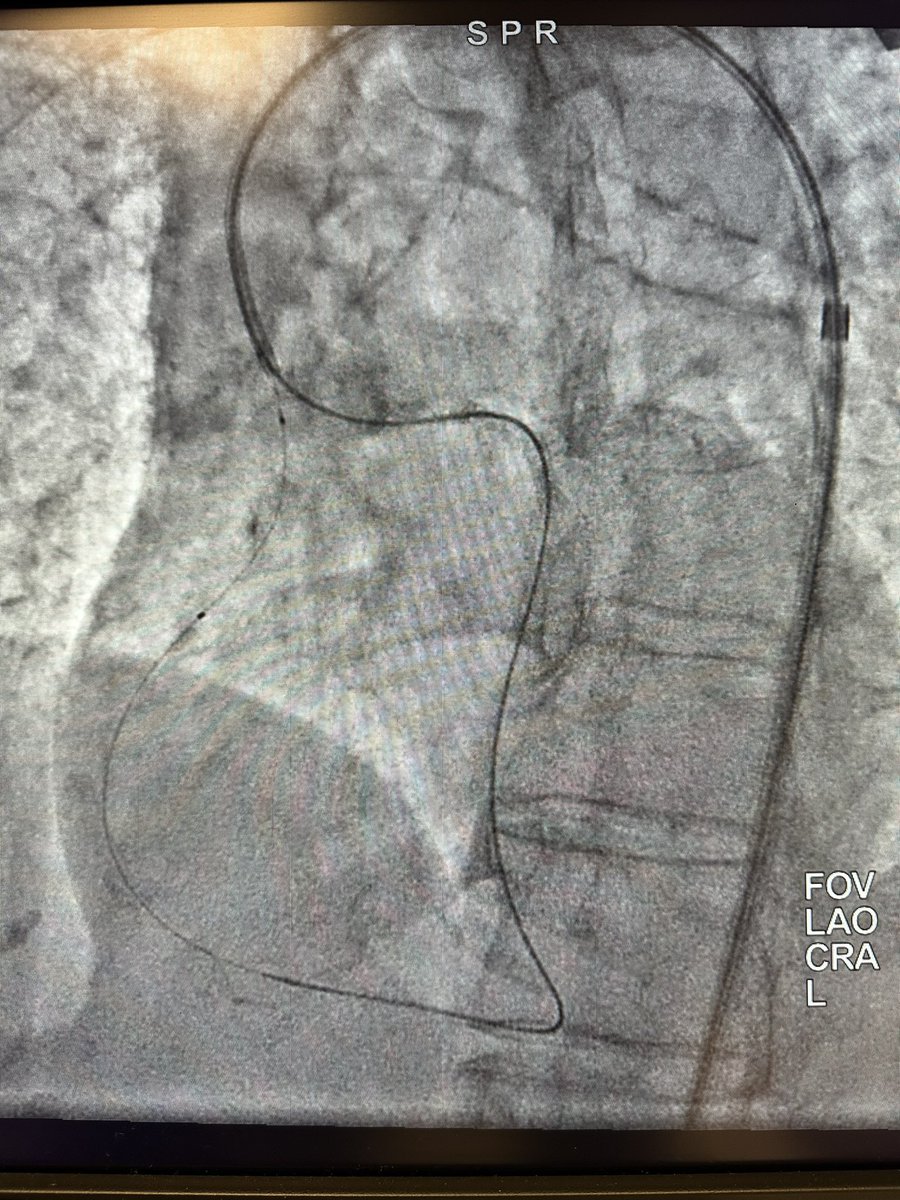

Interesting situation in patient with challenging access options with flush occluded ostial RCA. Able to wire retro and externalize in single EBU guide in the descending aorta before switching antegrade and stent.@jgpugedamd